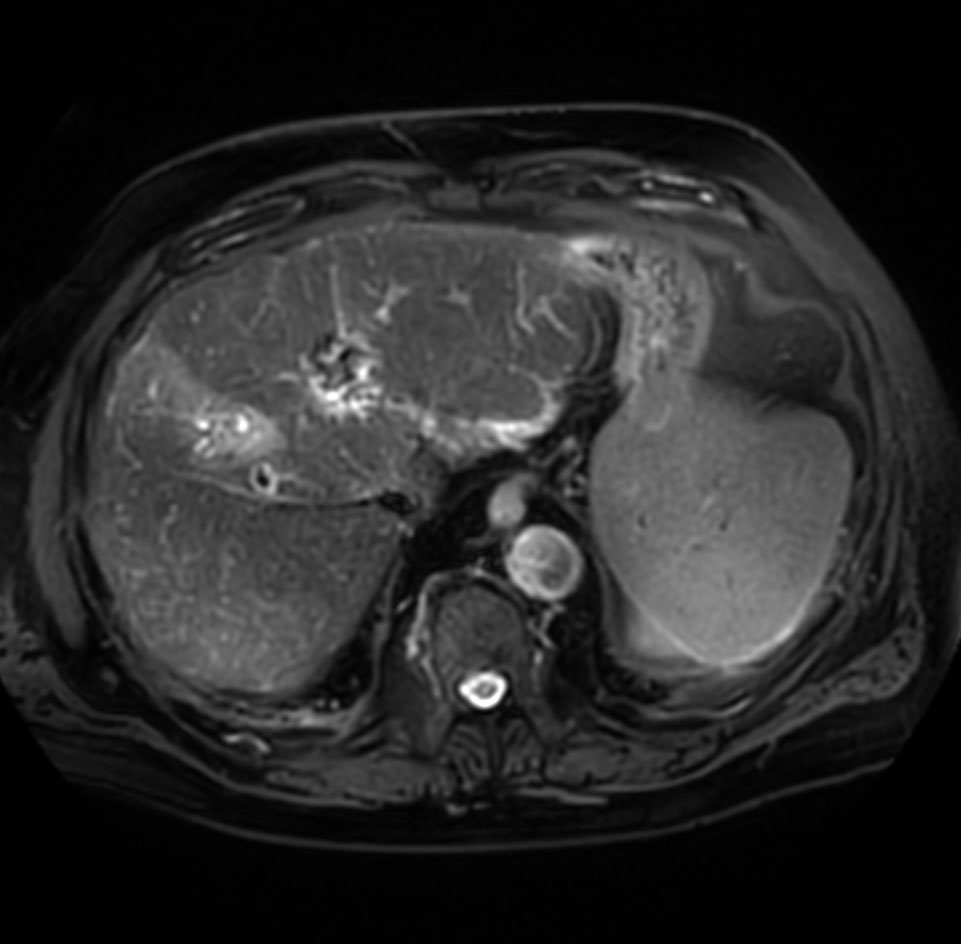

Axial T2w TSE

Axial T2w SPAIR - MultiVane XD